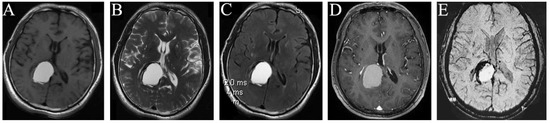

Figure 2.

MRI manifestations of the space-occupying intracranial fungal lesion on 9 July 2020. T1WI (A), T2WI (B), T2 Flair (C), and Contrast-enhanced T1 (D) show that the right occipital lobe occupation became obviously larger than before, with predominantly high signals on T1WI (A), T2WI (B), and T2 Flair (C), and equally enhanced signal on Contrast-enhanced T1 (D); SWI examination found no vascular diseases (E).

Imaging examination: the intracranial MRI revealed a space-occupying lesion with a regular shape and clear boundary in the right occipital lobe. Further, the corpus callosum and posterior horn of the right lateral ventricle were compressed. The occupation was 2.8 × 1.7 and 4.0 × 2.6 cm2 in size at the maximum imaging level on 21 October 2015 (Figure 1A–E) and 9 July 2020 (Figure 2A–E), respectively, with annular low signal shadow in the edge and small edema signal in the surrounding area, showing a high signal in the T2-weighted and T2 flair image and an equally high signal in the contrast-enhanced T1 image (Figure 1A–D and Figure 2A–D). The T1-weighted image of this occupation first revealed an equally low signal, and after the occupation became larger, it demonstrated a high signal (Figure 1A and Figure 2A). Moreover, the susceptibility-weighted imaging (SWI) examination found no vascular diseases (Figure 2E), and the CT revealed a low density of this occupation (Figure 1E).